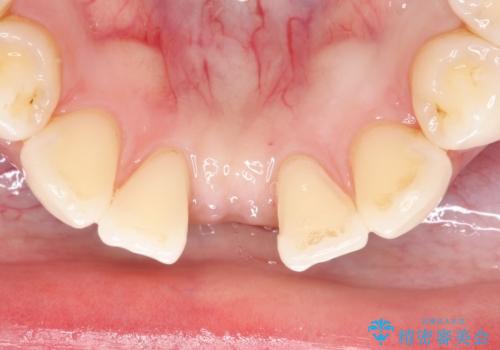

- 下顎前歯の欠損補綴を主訴として治療を行いました。

インプラントやクラウンブリッジは希望されず、接着ブリッジにて治療を行いました。

接着ブリッジは維持をレジン系のセメントのみに依存しているため脱離するリスクは高いです。

適応は下顎前歯の1歯欠損のみとしております。

リテーナー(支台歯)は1歯の方が長期予後が良いとされております。